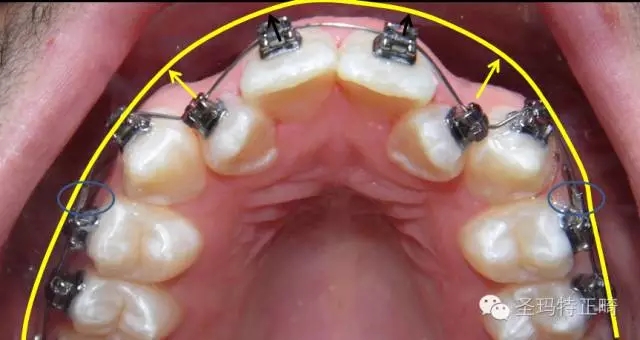

應(yīng)用舉例2 加速擴弓

如圖所示,先將支抗牙的牙絲入槽,把阻擋管置于支抗牙的近中端,并使牙絲位于前牙托槽外側(cè)約1~2毫米處,夾扁固定阻擋管。按照正常操作步驟,完成牙絲入槽,即可在阻擋管的幫助下開始更為有效的擴弓。